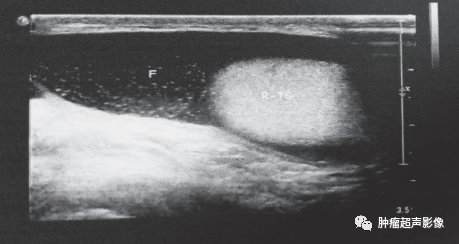

2、精索鞘膜积液:无回声位于睾丸上方或腹股沟区(一面靠水),呈圆形或梭形,边界清晰,光滑,位置可高可低,阴囊增大不明显。

精索鞘膜积液:一面靠水